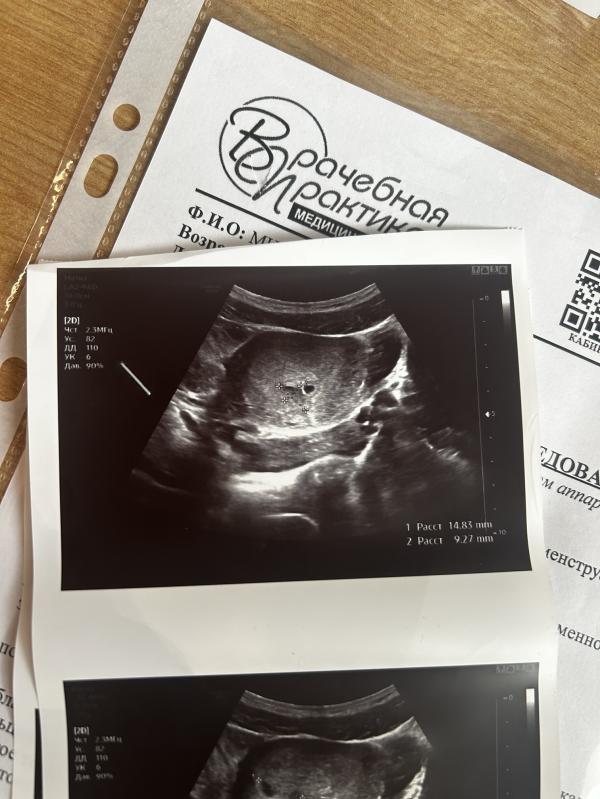

@lenasin на снимке узи слева от плодного яйца чёрный участок. Отслойка маленькая, а гематома большая

Написали, что желточный мешочек не определяется, может из-за этого так напугали? Гематома то фигня, она у большинства. Я думаю, еще рано, ни о чем не думайте, расслабляйтесь, берегите себя и через недельку еще на узи

По узи не вижу причин для выкидыша. Гематома у многих бывает – постельный режим, транексам если кровит.

Скорее вывод сделали не из за того что гематома, а из за того что срок 6-7 недель а эмбриончика нет ещё((( на 6 неделе уже сердечко можно услышать... А то что гематома, так она у многих. У меня тоже по УЗИ гематома есть, но при этом малыш растёт😌 здесь наверное только динамика покажет, появится ли эмбриончик ждать нужно🤞